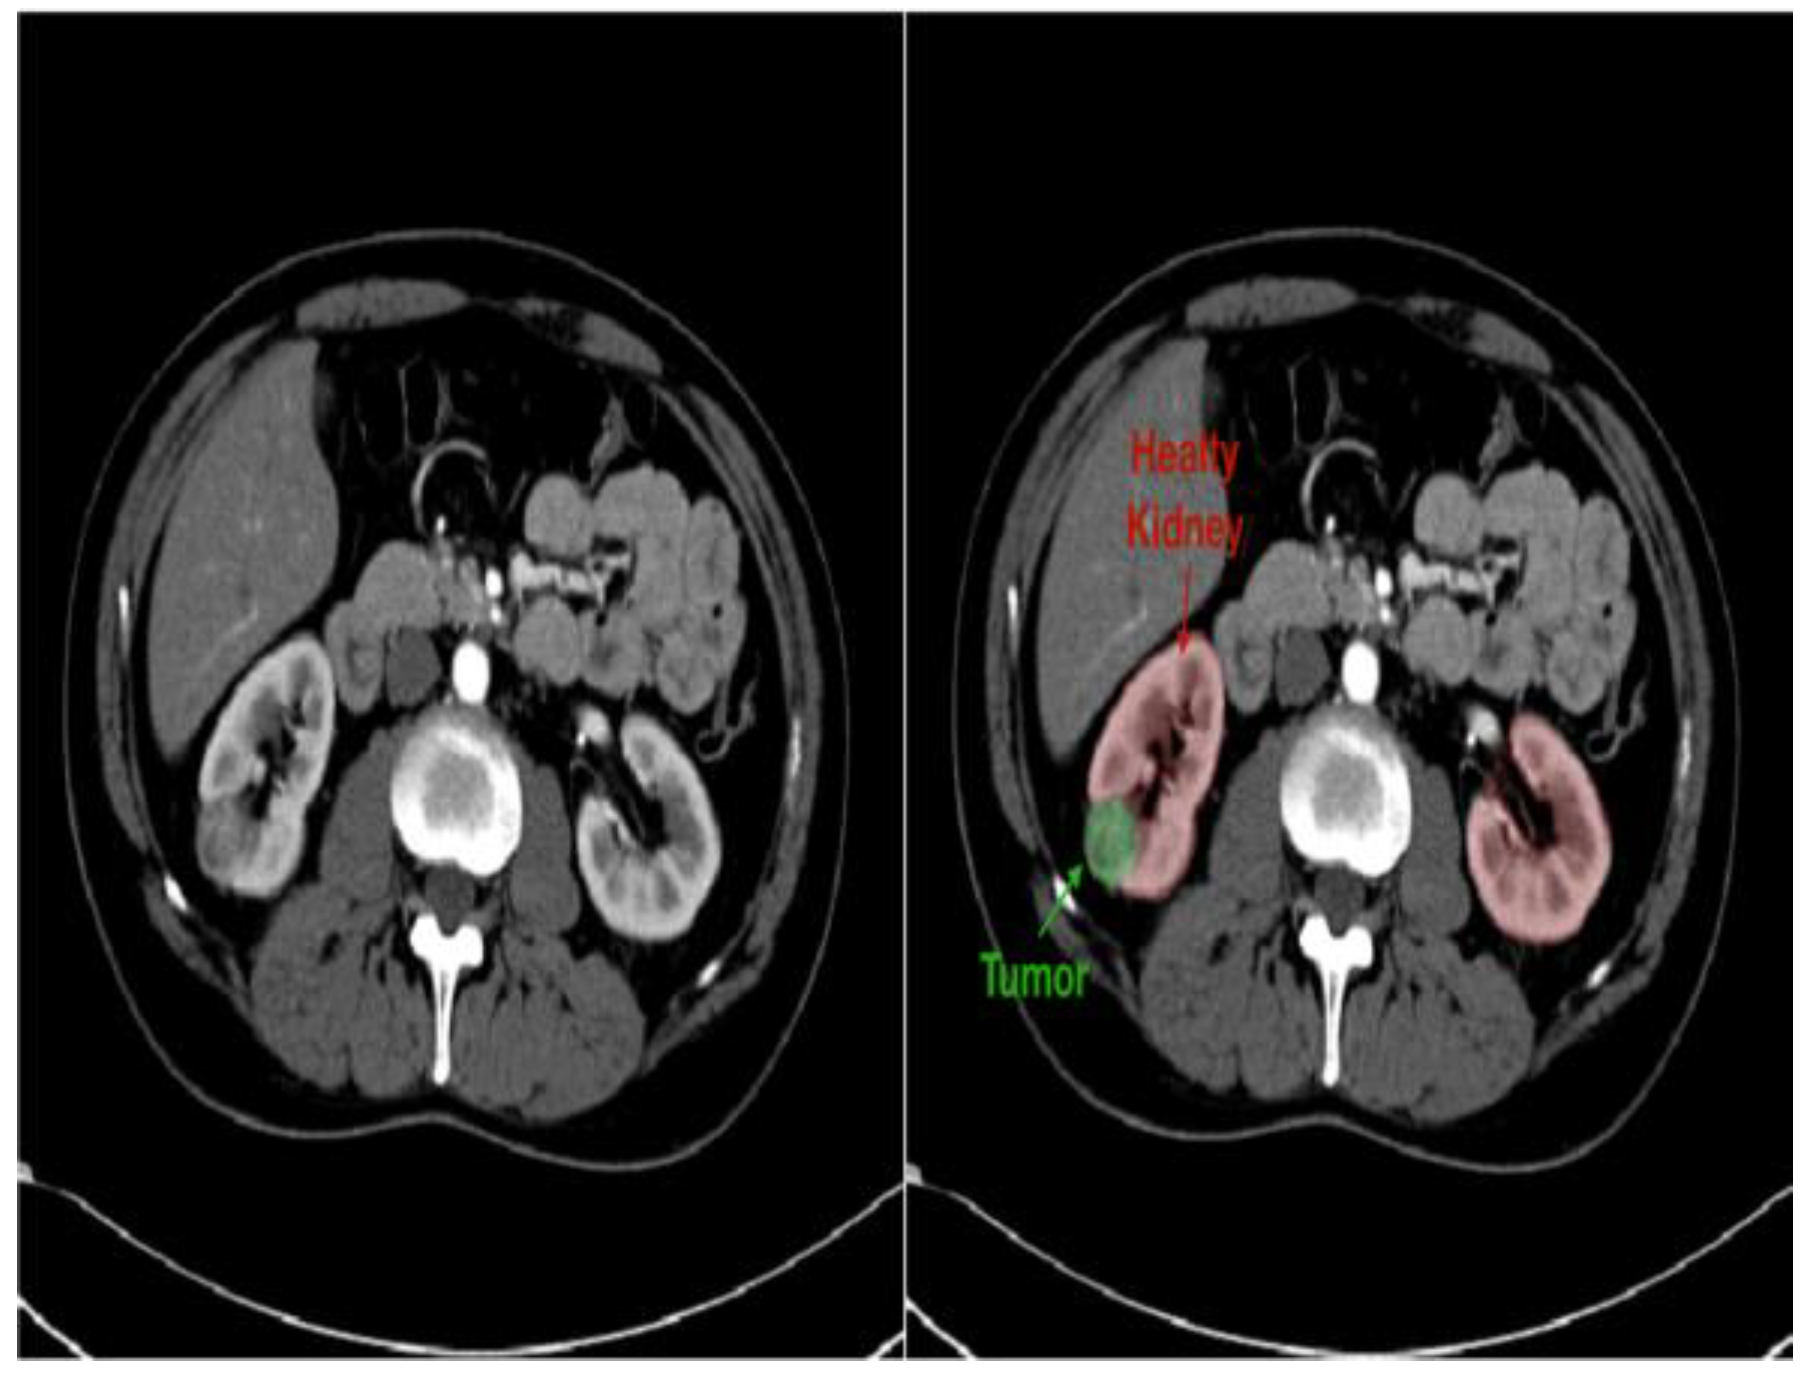

- Improved diagnostics: AI-driven image analysis tools can enhance the identification and description of pediatric kidney cancers and tumors. Radiologists can spot minor abnormalities, characterize renal masses, and estimate tumor burden more accurately using ML algorithms that have been trained on large datasets of pediatric renal images (Figure 7). AI algorithms enable the early identification of kidney cancers and tumors by methods including pattern recognition, masking, segmentation, and quantitative analysis, allowing for confident diagnosis and timely treatment [24].

- Personalized treatment planning: AI systems provide personalized therapy recommendations and perform the prognostic evaluation of patient-specific data, including clinical history, imaging results, and laboratory values. For young patients with kidney cancers, this customized strategy enables medical practitioners to maximize therapeutic efficacy, reduce treatment-related morbidity, and enhance long-term outcomes [43].